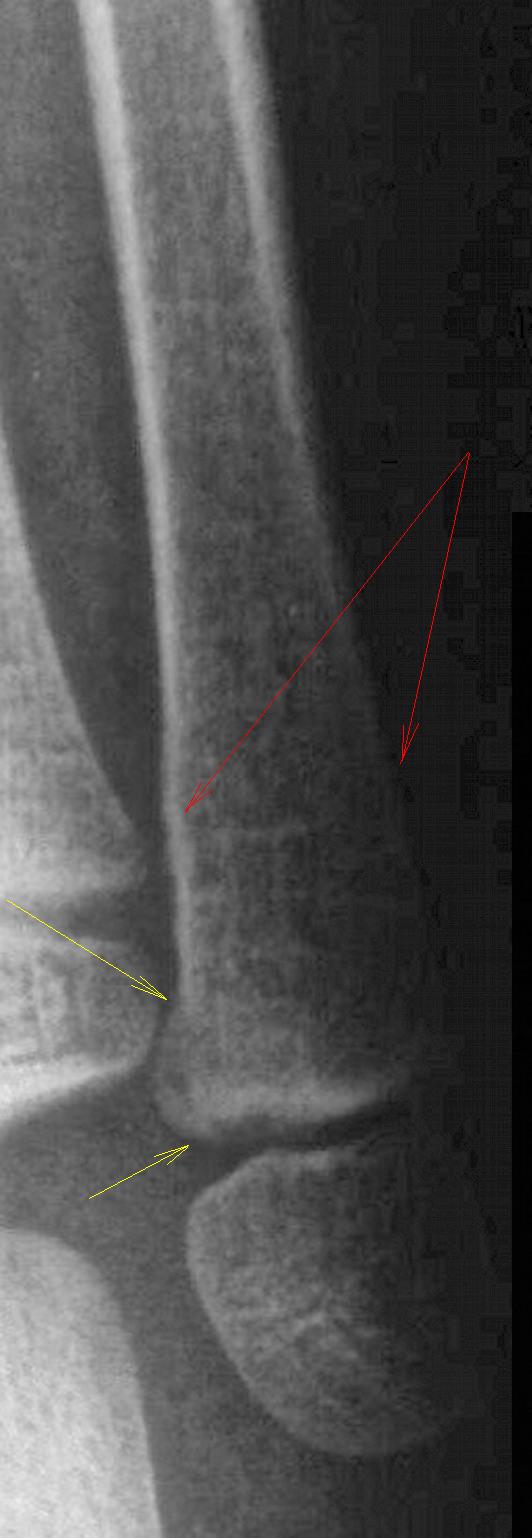

Ольга!

А Вы прицельно гляньте дистальную треть м/берцовой выше зоны росткового хряща.

Вас смущает это место (стрелки).

Я тоже поначалу обратил внимание, но:

1.снимок выполнен с небольшим поворотом стопы медиально.

2.клинически, со стороны латеральной лодыжки никакой боли нет.

Это место абсолютно нормально, у маленьких детей всегда так выглядит.

Да, эти два участка м/берцовой кости, вызвали у меня "законные сомнения", и дабы развеять сомнения, или подтвердить их, производство рентгенограмм в косых проекциях было-бы не лишним.